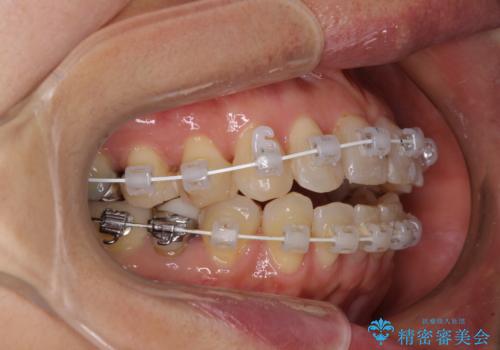

- 矯正装置

- 審美装置

- 前歯のデコボコを気にして来院された患者様です。

インビザラインでもワイヤー装置でも対応可能であったので、両者のデメリットをご説明し、選択していただくことになりました。

マウスピース矯正の装着時間の長さや自己管理の重要性を煩わしいと感じられ、低依存で確実に治療ができるワイヤー矯正を選択されました。

舌突出癖により、上下前歯がなかなか接触せずに治療期間を要しましたが、舌のトレーニングにより無事に治療を終えることができました。